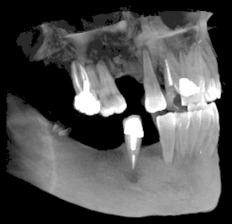

Денталните медици могат с лекота да правят всички необходими обработки и измервания на дигиталните зъбни снимки, което улеснява подготовката за лечебния процес на пациента.